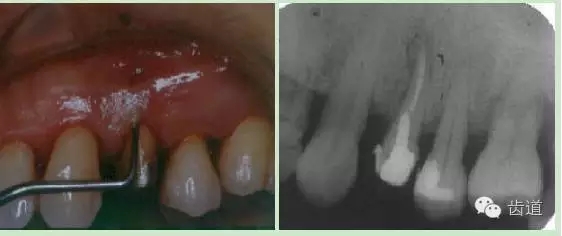

頰側(cè)牙齦相應(yīng)于根中部可見瘺管,周圍齦腫脹,輕壓少量溢膿。

瘺管處尖探針探入可達(dá)根面,略有粗糙感。

PD 頰側(cè)正中10mm,窄而深,袋口緊,附著喪失9 mm。探與瘺管相通,鄰面及腭側(cè)PD 3-4 mm,樁核冠,未粘合,正中咬合輕度早接觸。松動(dòng) Ⅰ°全口口腔衛(wèi)生較差,PLI: 2,牙石(++)

彩幻及X片: